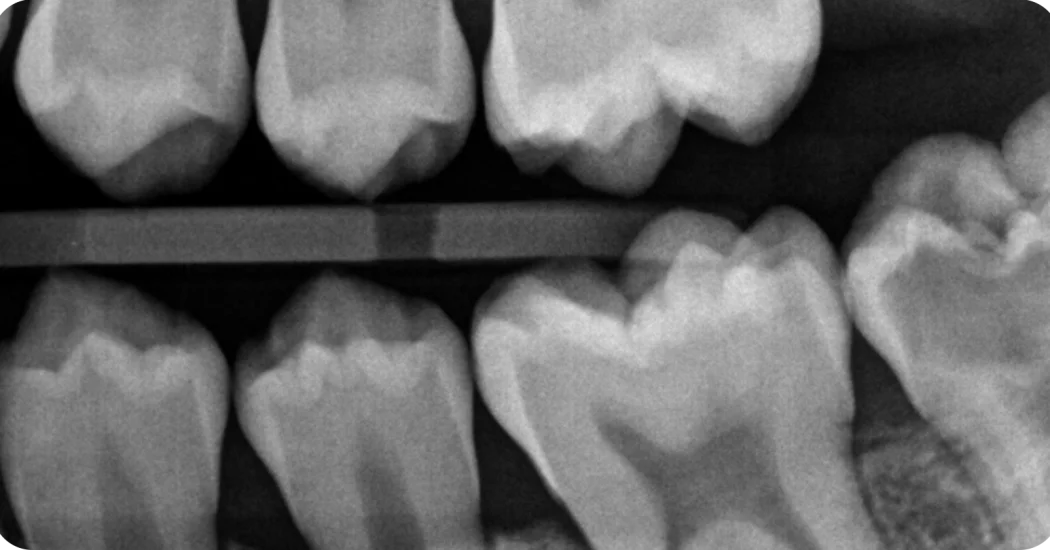

Pełna pulpotomia z użyciem Biodentine® XP w niedojrzałym zębie z przedwyrżnięciową resorpcją wewnątrzkoronową

W niniejszym studium przypadku dr Patel w pełni wykorzystuje właściwości terapeutyczne i mechaniczne Biodentine®, aby leczyć ząb dotknięty przedwyrżnięciową resorpcją wewnątrzkoronową (PEIR) u młodego pacjenta, którego głównym celem jest zachowania żywotności miazgi oraz integralności zęba.

Leczenie zachowawcze miazgi (VPT) ma na celu zachowanie miazgi, która pełni szereg istotnych funkcji, w tym dentynogenezę, obronę immunologiczną oraz propriocepcję. […] Jest to szczególnie ważne w przypadku zębów dotkniętych przedwyrznięciową resorpcją wewnątrzkoronową (PEIR), ponieważ często mają one niedojrzałe wierzchołki korzeni, a kontynuacja rozwoju korzenia jest w takich przypadkach bardzo korzystna. ”

W niniejszym studium przypadku dr Patel w pełni wykorzystuje terapeutyczne i mechaniczne właściwości Biodentine®, aby leczyć ząb dotknięty przedwyrznięciową resorpcją wewnątrzkoronową (PEIR) u młodego pacjenta. Głównym celem leczenia jest zachowanie żywotności miazgi oraz integralności zęba.